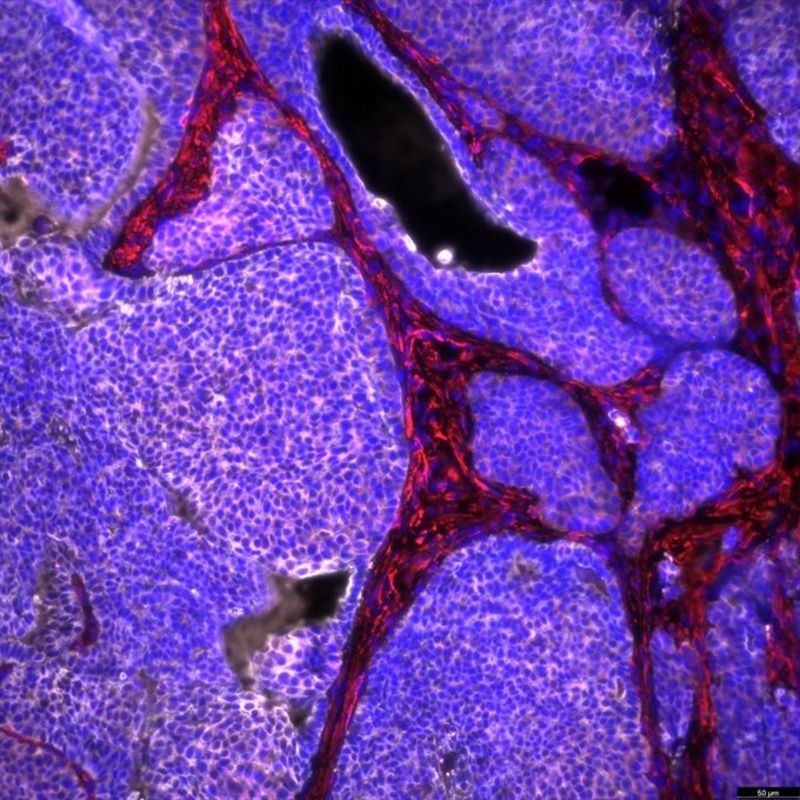

Cáncer de mama en ratón, con células tumorales en color blanco (Europa Press)

Cáncer de mama en ratón, con células tumorales en color blanco (Europa Press)El equipo examinó la incidencia (nuevos casos), las muertes, las consecuencias para la salud (años de vida ajustados por discapacidad) y los factores de riesgo para las personas de 14 a 49 años entre 1990 y 2019.